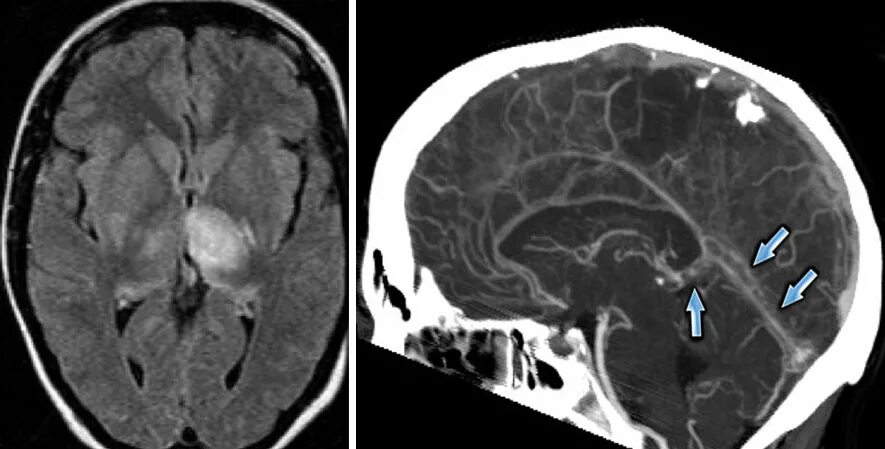

Синусы мозга мрт